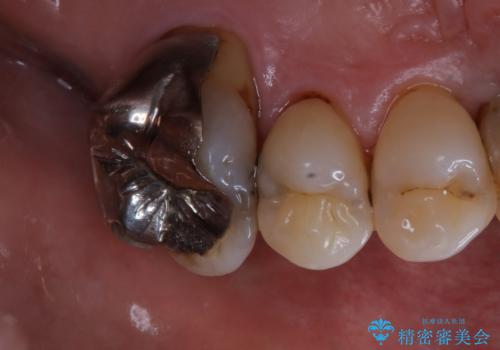

施術後の歯の表面に、茶色く色が残っている所がありますが、これは詰め物の変色の所と、虫歯になっている所です。以前に、CR(コンポジットレジン)による虫歯治療がされています。

CRは経年的劣化や、着色してしまうことがあります。PMTCでクリーニングを行うと、古いCRが目立つことがあるため、気になる際は詰め替えを行います。

茶色くなっている部分が、着色なのか、劣化なのか、虫歯によるものなのかは判別が難しいことがあります。そのため、定期的にPMTCを行うことで状態の確認が的確に行えます。

また、治療が開始される前などにも、全体的にクリーニングを行いご自身本来の歯の色、状態を精密に確認することが大切です。